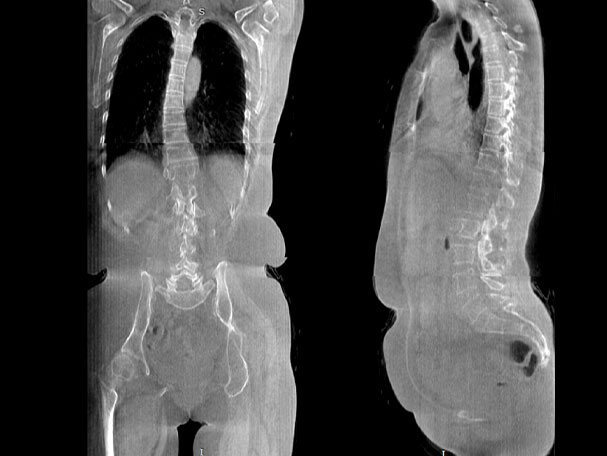

VR体绘制重建

气道三维影像重建